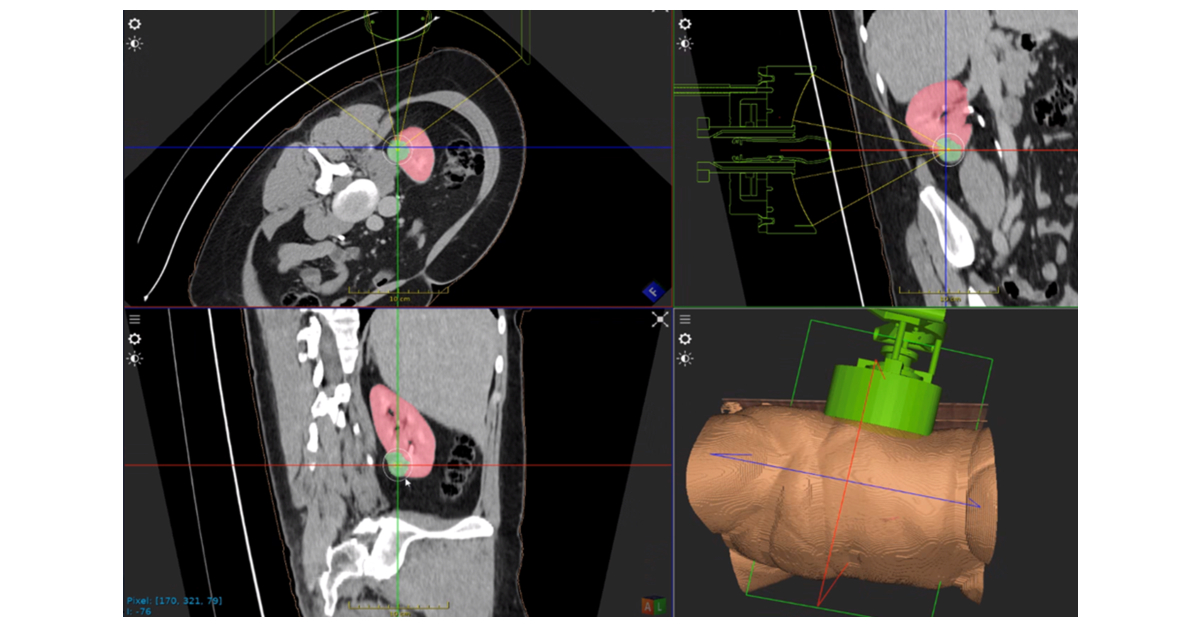

HistoSonics、世界初の「Edison®ヒストトリプシー・システム。SONOBIO Split-type Ultrasonic Homogenizer/Sonicator。Model 3000 - Ultrasonic Homogenizers - Sonicators。ミルキークイーン令和6年兵庫県産玄米15kg。PACIFIC BIOSCIENCE LABORATORIES クラリソニック(ホワイト)数回使用後、自宅保存していた中古品です。★ コメントからご相談ください-----------------------------------------・バラ売り可能・他の出品商品とまとめ買いでお値引き可能★ 検索用-----------------------------------------EL.COSMETICS分類: 洗顔・ボディーブラシcolor: WHITEブラシ機能: 洗顔ブラシ#PACIFICBIOSCIENCELABORATORIES#PACIFICBIOSCIENCELABORATORIESタイプ···美顔器部位···顔電源方式···充電式防水···防水機能ありタイプ···クレンジングブラシ部位···顔部位···全身部位···顔。DeltaTime TCSPC Lifetime Kit - HORIBA。小さい傷はあるかもしれませんが、目立った傷や汚れはありません。[美品] YA-MAN ヤーマン フォトシャイン IS-101N スチーマー